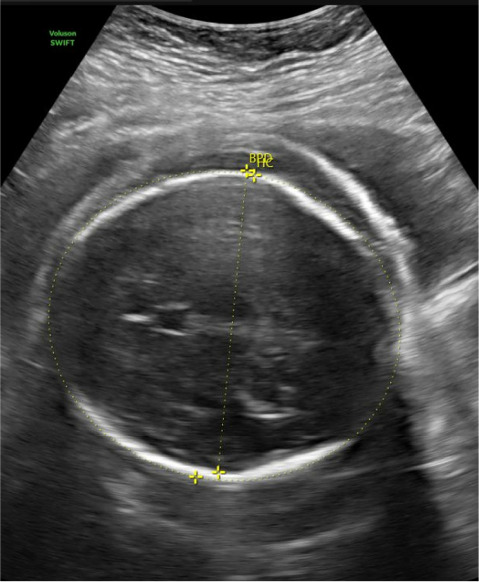

Nonimmune hydrops fetalis (NIHF) refers to the pathologic accumulation of fluid within the fetus due to causes other than red cell alloimmunization and now accounts for up to 90% of fetal hydrops cases. Fetal hydrops is associated with significant morbidity and mortality, and the exact prognosis is largely dependent on the underlying etiology. The most common etiologies include cardiovascular causes and chromosomal or genetic abnormalities. Despite this, diagnostic testing with karyotype or chromosomal microarray only identifies approximately 25% of cases, and up to 20% of cases remain idiopathic or unknown. We report the first known case of NIHF related to a NOTCH1 pathogenic variant. In this case, NIHF was diagnosed at 30 weeks' gestation in a fetus with low-risk prenatal genetic screening, noncontributory anatomic survey, and normal chromosomal microarray. The hydrops was uniquely localized to scalp edema and pleural effusions requiring bilateral thoracentesis and never progressed to involve pericardial effusion or ascites. Whole exome sequencing diagnosed a novel pathogenic variant in the NOTCH1 gene. This is the first reported case of NIHF in the setting of NOTCH1 pathogenic variant and is an important addition to the existing literature on this incredibly diverse, high-risk pathology.

Abstract Image